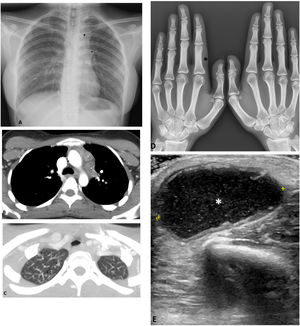

A) Radiografía de tórax demuestra un moderado ensanchamiento mediastínico superior izquierdo (*), así como un hilio izquierdo prominente de morfología nodular (flecha). B) La TC torácica en la ventana de mediastino muestra adenopatías mediastínicas izquierdas, con centro hipodenso. C) En la TC torácica en la ventana de pulmón se observa algún nódulo subcentimétrico en el ápex derecho (flechas). D) En la radiografía de las manos se aprecia mínima tumefacción de partes blandas a nivel de la falange proximal del segundo dedo de la mano izquierda (*). E) La ecografía del codo derecho muestra la presencia de una colección (*), hipoecogénica y con ecos puntiformes en su interior, de 35mm de diámetro máximo, ubicada en la partes blandas del codo derecho y compatible con absceso de partes blandas.

Presentamos un caso de una paciente de 20 años, natural de Bangladesh, sin hábitos tóxicos, sin antecedentes patológicos de interés y sin medicación habitual. Consultó por dolor, tumefacción y enrojecimiento a nivel del dedo índice de la mano izquierda y aparición de lesión nodular dolorosa de consistencia blanda, abscesificada, de 6cm de diámetro, de un mes de evolución a nivel del codo derecho, acompañada de pérdida de peso (4kg) de 6 meses de evolución. En el estudio complementario se incluyó una analítica sanguínea en la que destacaba una velocidad de sedimentación globular 110mm/h, sin ninguna otra alteración en el hemograma, el proteinograma y la función renal, hepática y autoinmune. La determinación de interferón-γ (IGRA) y de virus de la inmunodeficiencia humana fue negativa. La prueba de tuberculina resultó positiva (20×22cm). La radiografía de tórax mostró ensanchamiento mediastínico superior izquierdo e hilio izquierdo prominente de morfología nodular (fig. 1A). La tomografía computarizada de tórax mostró adenopatías mediastínicas izquierdas con centro hipodenso (fig. 1 B) y nódulos pulmonares subcentimétricos en el ápex derecho (fig. 1 C). Se realizó una radiografía de la mano izquierda donde se aprecia una mínima tumefacción de partes blandes a nivel de la falange proximal del segundo dedo (fig. 1 D). Se solicitó punción guiada por ecografía a nivel de la zona epicondílea de la extremidad superior derecha, que confirmó una colección hipoecogénica con ecos internos y paredes discretamente engrosadas de unos 36×32,5×20,5mm de diámetro (fig. 1 E). Tras la punción aspirativa con aguja fina, la tinción de Ziehl-Neelsen resultó negativa, siendo positiva la PCR para Mycobacterium tuberculosis (M. tuberculosis). Pendiente del resultado del cultivo de micobacterias, debido al contexto clínico de la paciente, se decidió iniciar tratamiento tuberculostático con 4 fármacos, isoniazida, rifampicina, pirazinamida y etambutol (HRZE), y solicitar estudio genotípico de resistencias a los fármacos de primera línea. Se detectó mutación del gen KatG, que confiere resistencia a la isoniazida, que posteriormente se confirmó con el antibiograma del cultivo. Con estos resultados se añadieron linezolid y moxifloxacino los primeros 2 meses al tratamiento convencional. Completó un año con moxifloxacino, rifampicina y etambutol. Tras las 3 primeras semanas de tuberculostáticos, la paciente notó una mejoría progresiva, con regresión casi total de los signos inflamatorios de la falange proximal y del absceso. Al finalizar el tratamiento también se objetivó resolución radiológica.